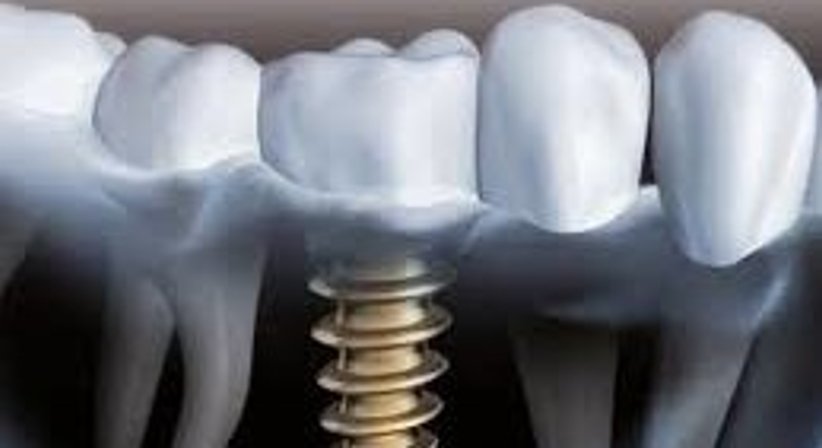

Bei einem Implantat handelt es sich um eine künstliche Zahnwurzel aus Titan, die im Rahmen eines oralchirurgischen Eingriffs in den Kieferknochen eingesetzt wird, um einen fehlenden Zahn zu ersetzen. Das Implantat verbindet sich mit dem umgebenden Knochen und dient nach der Einheilphase als Verankerung für festsitzenden (Kronen, Brücken) oder herausnehmbaren Zahnersatz (Prothesen).

Sobald das Implantat im Knochen eingeheilt ist, wird ein Aufbauteil mit dem Implantat verbunden. Auf diesem wird später der Zahnersatz (z.B. Zahnkrone) aufgesetzt. Im letzten Schritt erfolgt die Versorgung mit dem prothetischen Zahnersatz, welcher individuell hergestellt und hinsichtlich aller wichtiger Details präzise an die spezifischen Voraussetzungen des Patienten angepasst wird, sodass der implantatgetragene Zahnersatz später nicht von den Nachbarzähnen zu unterscheiden ist.